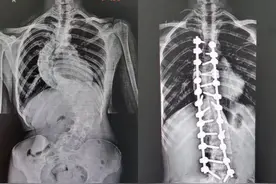

长沙晚报掌上长沙7月29日讯(全媒体记者 傅容容 通讯员 章茹)“9月开学,我可以自信地回到校园了!”今日,在湖南省第二人民医院脊柱外科,来自溆浦县的16岁女生小琳(化名)非常开心。被脊柱侧弯困扰多年的她,终于挺直了腰杆,“长高”6厘米。

暑假期间,来自溆浦县的小琳(化名)同学在湖南省第二人民医院“长高”了6厘米。今年16岁的小琳在4年前因为腰背部反复疼痛,在当地确诊为脊柱侧弯畸形。由于家庭条件限制,加上学业紧张,一直没有进行系统的治疗。疾病给小琳的生活蒙上了一层阴霾。

来源:【华声在线】华声在线7月30日讯(全媒体记者 李琪 通讯员 章茹 黄艳 张警盈 曾星怡)“还有一个月开学,我可以自信地回到校园啦!”7月30日,湖南省第二人民医院脊柱外科,来自怀化溆浦县的16岁女生罗小琳(化名)开心地说道。